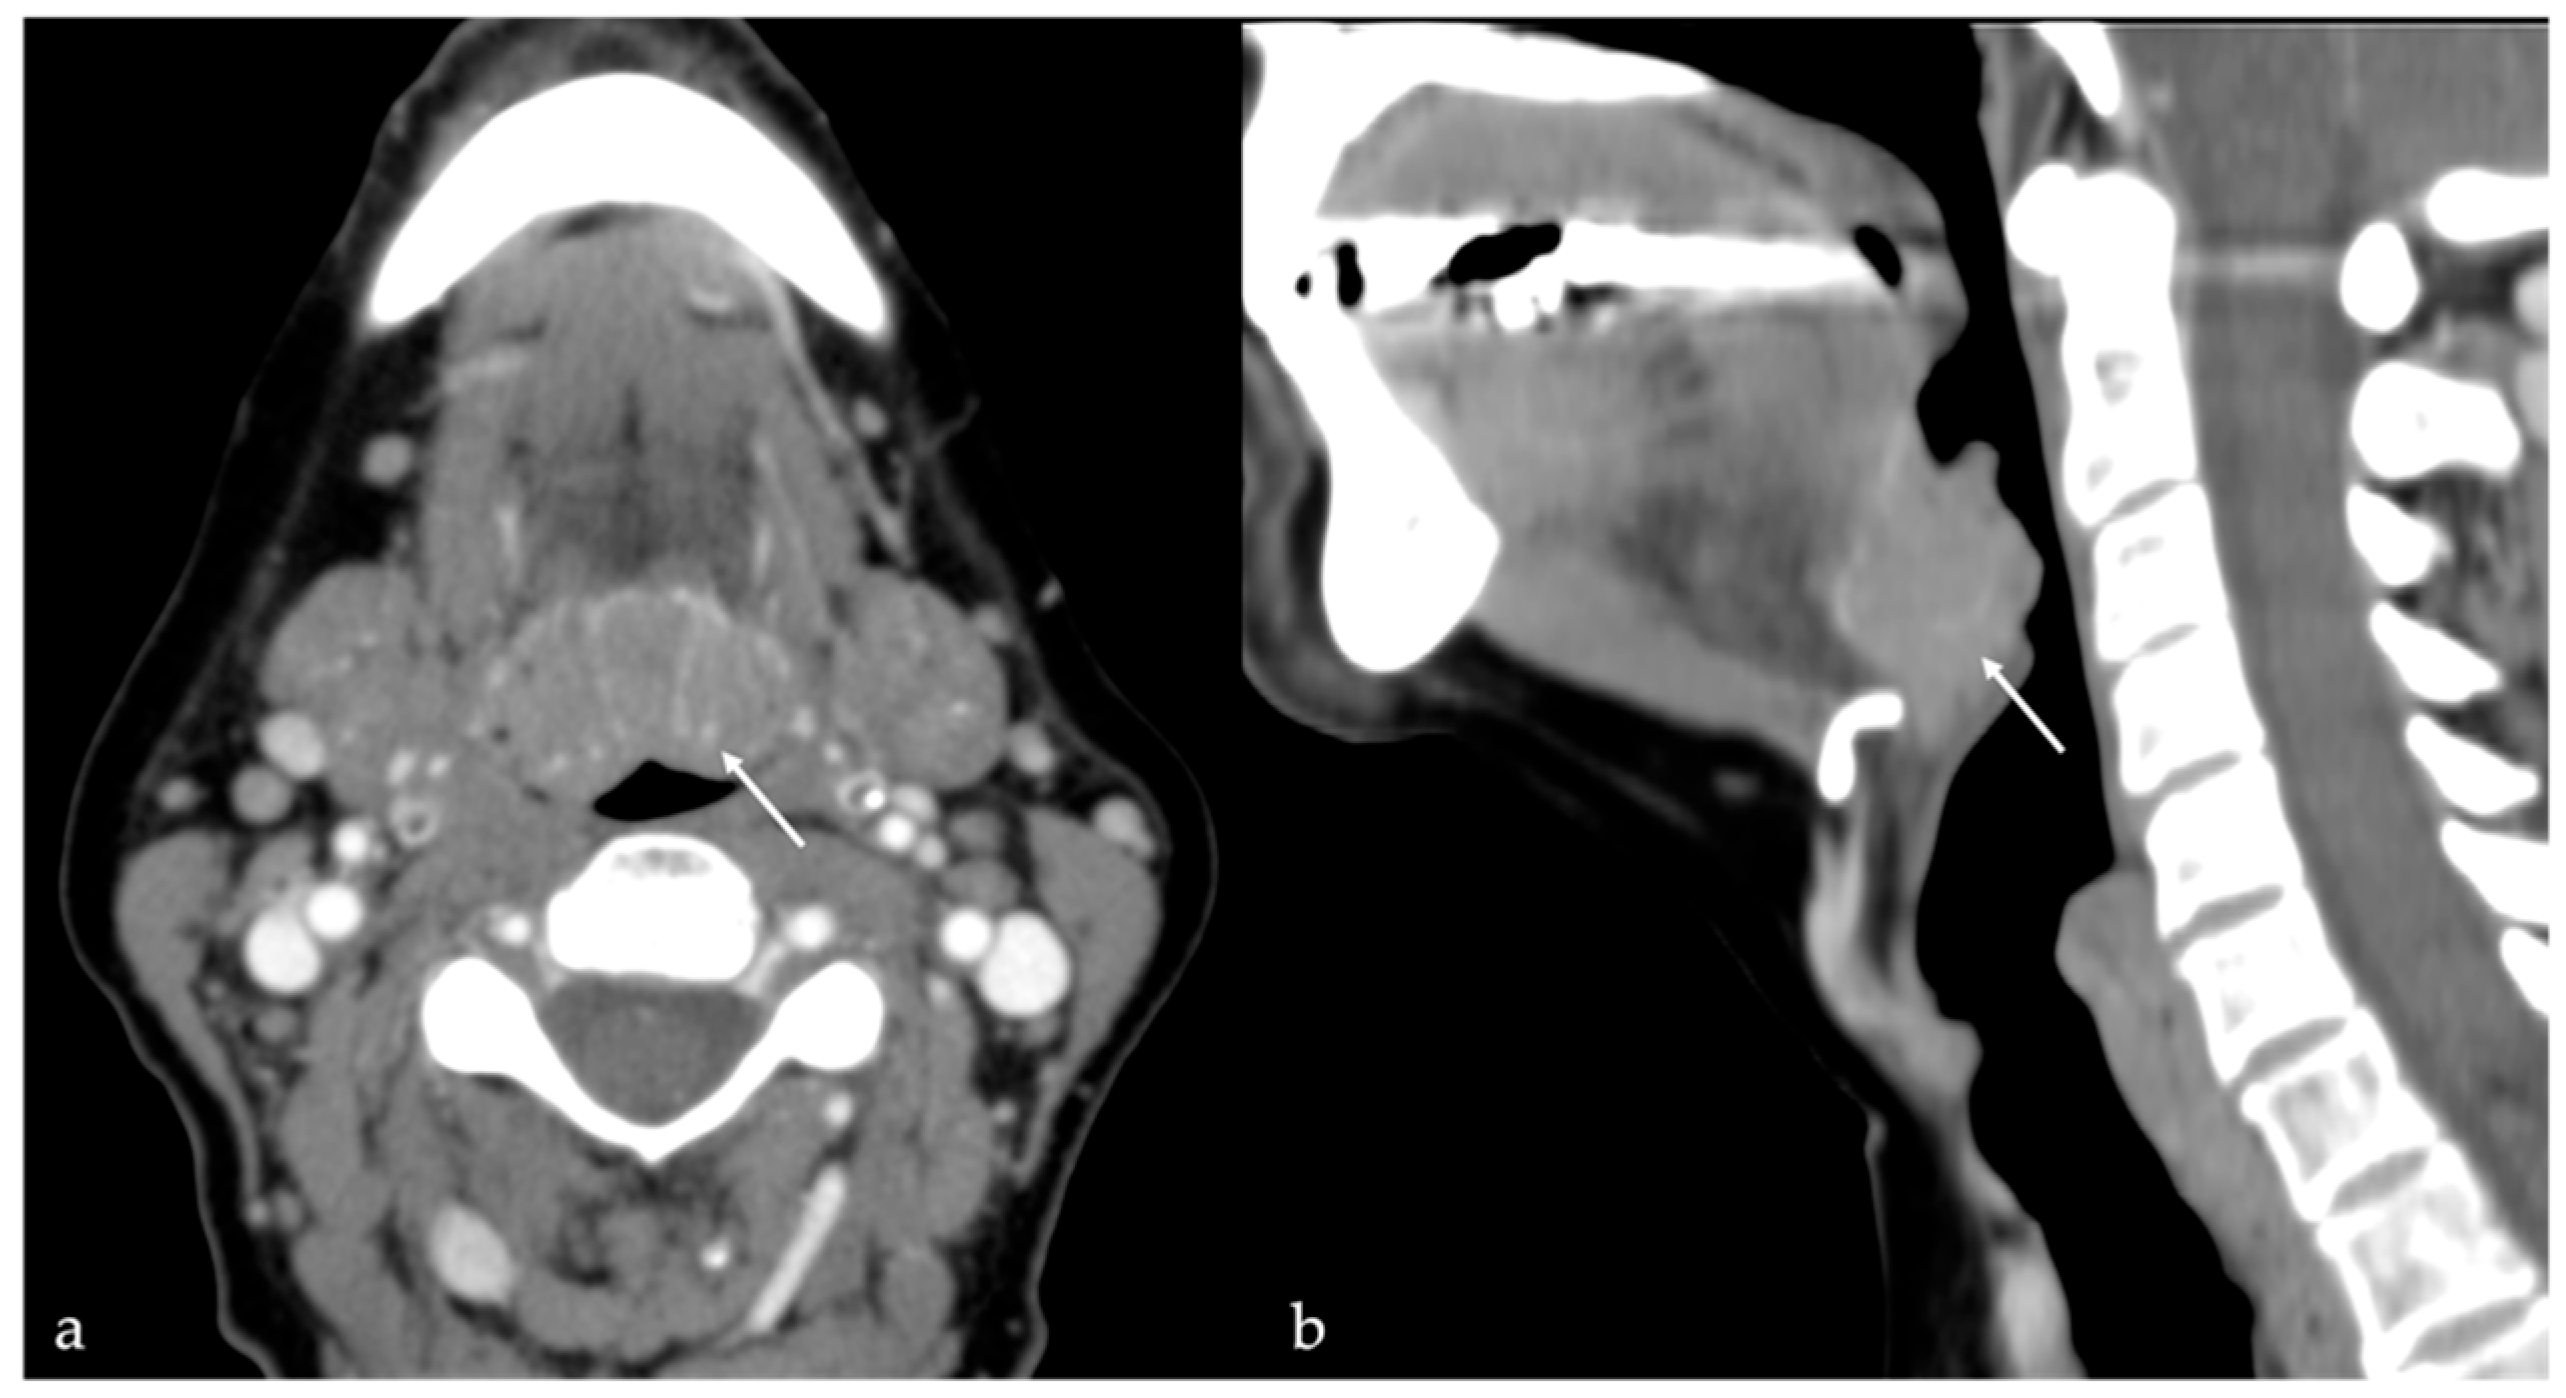

5.3. Arteriovenous Malformations

| Arteriovenous malformation [6,12] | MRA: arterial feeding vessel, nidus, and venous drainage vessels MRI: flow voids | Other vascular malformations |